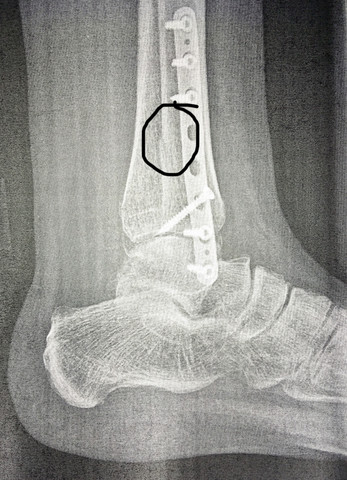

Chronik Einer Sprunggelenkfraktur Sky Junkies